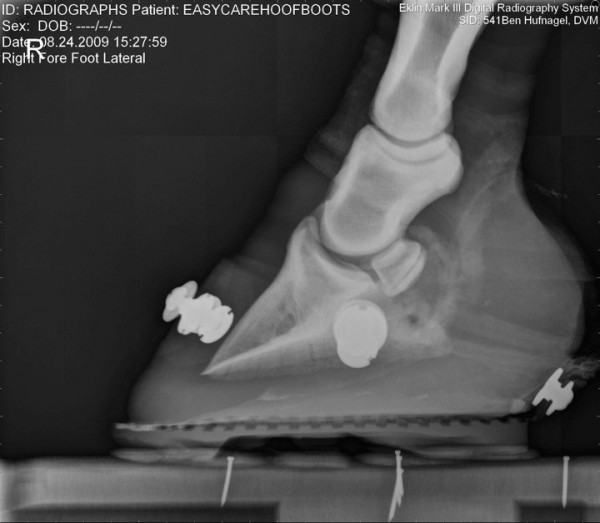

Společnost EasyCare si dělá vlastní průzkumy-výzkumy… zde jsou zajímavé fotografie jak to vypadá když je kopýtko v botě, zůstává ve svém přirozeném tvaru, kopytní mechanismus je neomezený a kůň ho má možnost plně přirozeně využívat 🙂